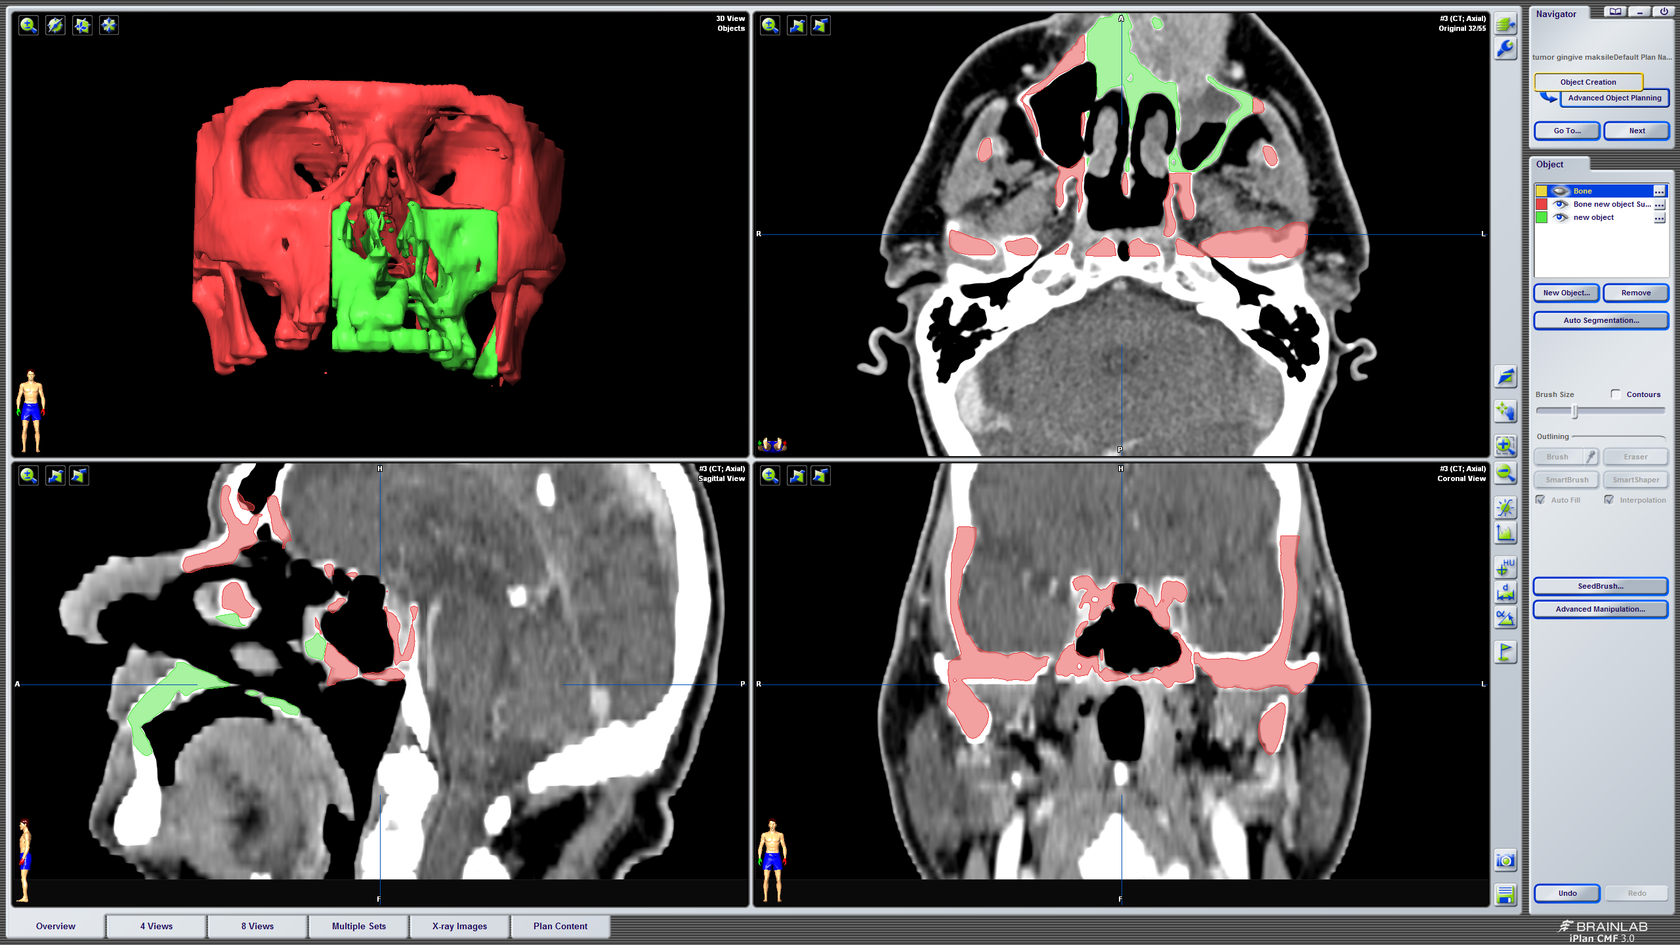

Kompjutorsko planiranje i simulacija

3D kompjutorsko planiranje rekonstrukcije defekta gornje čeljusti